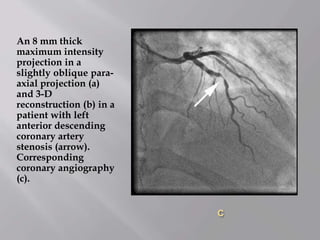

An 8 mm thick

maximum intensity

projection in a

slightly oblique para-

axial projection (a)

and 3-D

reconstruction (b) in a

patient with left

anterior descending

coronary artery

stenosis (arrow).

Corresponding

coronary angiography

(c).